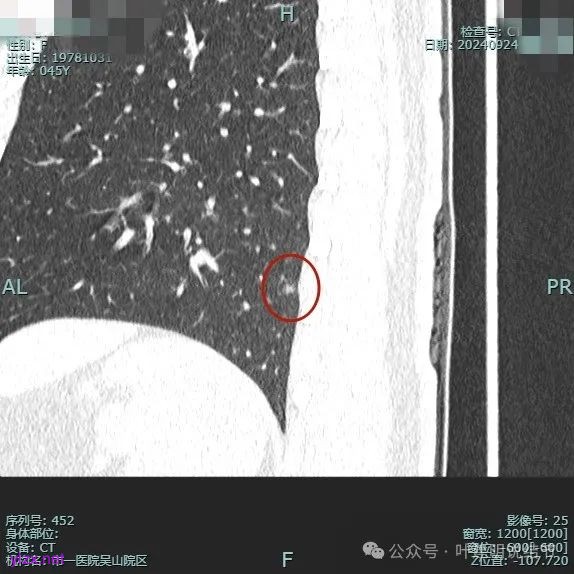

病灶2:

右中叶内侧段可见混合密度结节,大部分实性,形态与下叶背段的类似。

病灶3:

左下叶基底段微小结节,也是混合密度偏实性,瘤肺边界稍不清,与右侧的是类似形态的。